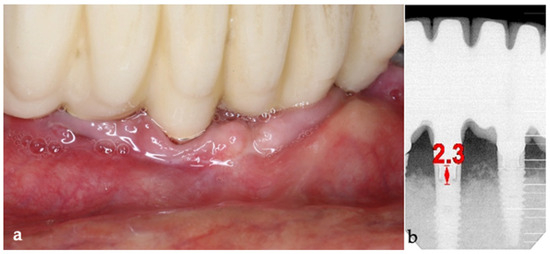

The surgical step began with local anesthesia (Lidocaine 2% with 1:100,000 epinephrine—Henry Schein Inc., New York, NY, USA) locally administered; the screw-retained crowns on the implants were removed to facilitate proper surgical access (Figure 9). The surgical site was assessed in order to provide a minimally invasive buccal flap design, which was favorable in this case, as it effectively executed the Quadrant protocol.

Then, the BSF was reflected to the lingual side (Figure 10c,d), exposing the surgical and infected site. Significant calculus deposits and plaque were noted on and around the implant surfaces. Then, with the screwed pin (hinge) in position, the implantoplasty was performed through the Quadrant protocol using the novel iMPACT device to renew the implant surface, transform it into a machined surface, and contour the surrounding bone (Figure 11).

The same protocol mentioned above was used. A five-day antibiotic regimen was administered prior to the surgical procedure. At the surgery, the site had no suppuration and minimal BoP; the implants #33, #36, #37, #44, and #47 were removed, and new implants were placed to provide a new rehabilitation. For the site #41 (without mobility and severe bone loss), following prosthesis and abutment removal (Figure 17a,b), a BSF with two crestal extensions was made around the implants (Figure 17c,d), facilitating optimal access and flap management during the surgical procedure, eliminating the need to retract two flaps, as a midcrestal flap requires. The flap was retracted lingually; the granulation tissue was removed, and the contaminated implant surface fully exposed (Figure 17d).

The specialized “pin” guide was attached to the implant and contacts in juxtaposition with the surface of the implant–abutment connection platform (Figure 17e,f). The guide, extending the long axis of the implant, was used to position and control the iMPACT device’s rotational movement (Figure 17g,h), with cutting blades extended to maximum capacity (Figure 17h,i). Initial rotation levels of the alveolar bone (Figure 17j,k) permitted controlled mechanical injury to the bone, initiating the bone healing response, known as “Bone Regeneration Induction,” which is the second principle of the “Quadrant protocol.” Incremental machining at speeds between 200–300 RPM with torque settings of 7–9 N·cm removed contaminated implant threads (Figure 17l). The cutting action of the iMPACT prevents heating during manipulation, and the suction airflow removes macroparticles without the need for irrigation; thus, producing macro-sized particles removed via suction. The non-irrigation approach established an oxidative environment conducive to passivation layer formation. Post-machining (Figure 17l), the site was thoroughly cleaned and dried, and bleeding was stimulated and associated with the bone particulate graft (Figure 17m). The flap was repositioned, and abutments were placed back to keep and hold it in position for the final suture (Figure 17n). Antibiotics were continued postoperatively for three additional days.

Figure 17. Step-by-step treatment for peri-implantitis using the iMPACT and Quadrant protocol. (a) Initial clinical evaluation; (b) Removing the abutments for peri-implantitis treatment; (c,d) BSF raised for implant exposition; (e) Insertion of the hinge (pin), which was crewed into the implant; (f) Hinge in position; (g,h) iMPACT adapted to the hinge; (i) iMPACT spinning for implantoplasty; (j) The implant surface was smoothed, and bone around the implant was gently cut (osteotomy); (k) occlusal view showing the osteotomy; (l) implantoplasty finished—implant surface is completely smoothed (machined); (m) Bone graft; (n) Suture and abutments were repositioned.